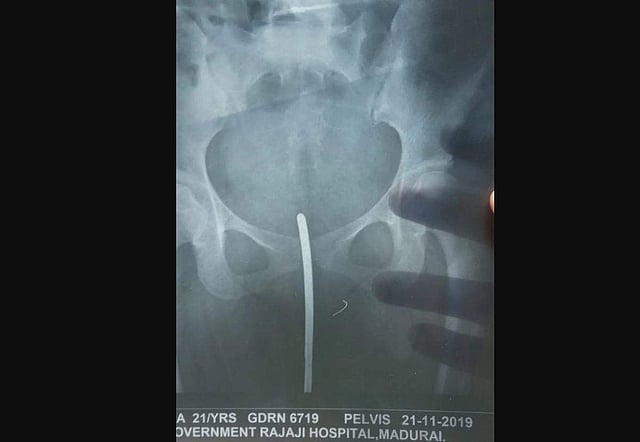

Sources at the Madurai hospital said Ramya was brought there at around 12.30 am on Thursday with the broken piece of needle intact in her pelvic bone. (Photo | EPS)

MADURAI/RAMANATHAPURAM: A suture needle which "accidentally" broke at the time of vaginal suturing performed after childbirth on a 21-year-old woman was removed from her pelvic bone by doctors at Government Rajaji Hospital on Thursday.

"As Ramya continued to bleed profusely the next day, the PHC staff referred her to the Government District Headquarters Hospital in Ramanathapuram around 3.30 pm. At around 9.30 pm, we learnt about the presence of a broken needle in her pelvic bone from X-ray images," Karthikeyan told Express. Early on Thursday, Ramya was shifted to the government hospital in Madurai.

Sources at the Madurai hospital said Ramya was brought there at around 12.30 am on Thursday with the broken piece of needle intact in her pubic bone. The needle had broken while performing episiotomy (a surgical incision made at the opening of the vagina during childbirth, to aid a difficult delivery and prevent rupture of tissues), sources said.

A team of doctors, including obstetrician/gynaecologist, urologist, gastroenterologist and anaesthetist, performed an hour-long surgery and removed the broken needle.